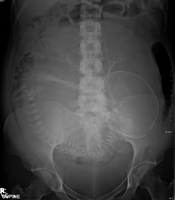

Abdominal radiograph of a pregnant woman, a procedure that should be performed only after proper assessment of benefit versus risk